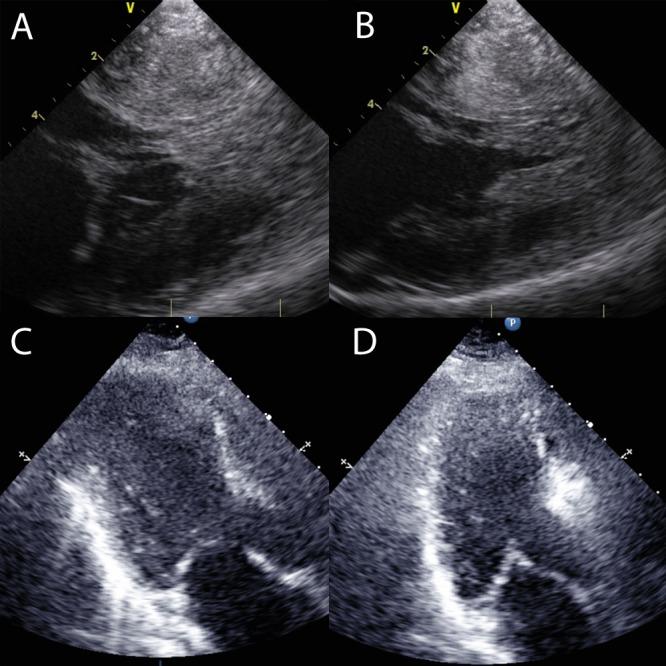

Alcohol septal ablation (ASA) in hypertrophic obstructive cardiomyopathy reduces left ventricular outflow tract gradients. A third of patients do not respond; inaccurate localisation of the iatrogenic infarct can be responsible. Transthoracic echocardiography (TTE) using myocardial contrast can be difficult in the laboratory environment. Intra-cardiac echocardiography (ICE) provides high-quality images. We aimed to assess ICE against TTE in ASA. The ability of ICE and TTE to assess three key domains (mitral valve (MV) anatomy and systolic anterior motion, visualisation of target septum, adjacent structures) was evaluated in 20 consecutive patients undergoing ASA. Two independent experts scored paired TTE and ICE images off line for each domain in both groups. The ability to see myocardial contrast following septal arterial injection was also assessed by the cardiologist performing ASA. In patients undergoing ASA, ICE was superior in viewing MV anatomy (P=0.02). TTE was superior in assessing adjacent structures (P=0.002). There was no difference in assessing target septum. Myocardial contrast: ICE did not clearly identify the area of contrast in 17/19 patients due to dense acoustic shadowing (8/19) and inadequate opacification of the myocardium (6/19). ICE only clearly localised contrast in 2/19 cases. ICE does not visualise myocardial contrast well and therefore cannot be used to guide ASA. TTE was substantially better at viewing myocardial contrast. There was no significant difference between ICE and TTE in the overall ability to comment on cardiac anatomy relevant to ASA.

酒精间隔消融术(ASA)用于肥厚性梗阻性心肌病可降低左心室流出道梯度。三分之一的患者无反应,这可能是医源性梗死定位不准确所致。在实验室环境中,使用心肌造影剂的经胸超声心动图(TTE)可能存在困难。心内超声心动图(ICE)可提供高质量图像。我们旨在评估在ASA中ICE与TTE的效果。对连续20例接受ASA的患者评估ICE和TTE评估三个关键区域(二尖瓣(MV)解剖结构和收缩期前向运动、目标间隔可视化、相邻结构)的能力。两位独立专家对两组中每个区域的TTE和ICE配对图像进行离线评分。进行ASA的心脏病专家还评估了间隔动脉注射后观察心肌造影剂的能力。在接受ASA的患者中,ICE在观察MV解剖结构方面更具优势(P = 0.02)。TTE在评估相邻结构方面更具优势(P = 0.002)。在评估目标间隔方面没有差异。心肌造影:由于浓密的声学阴影(19例中的8例)和心肌显影不充分(19例中的6例),ICE未能在19例患者中的17例中清晰识别造影剂区域。ICE仅在19例中的2例中清晰定位造影剂。ICE对心肌造影的可视化效果不佳,因此不能用于指导ASA。TTE在观察心肌造影方面明显更好。ICE和TTE在对与ASA相关的心脏解剖结构进行总体评价的能力上没有显著差异。